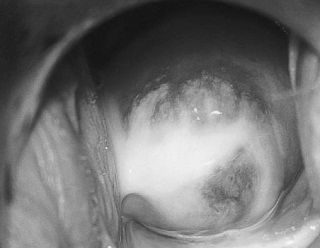

Кольпіт: фото

Зазвичай досвідченому гінеколога не складає труднощів діагностувати кольпіт. Огляд пацієнтки на кріслі проводиться за допомогою стандартних гінекологічних дзеркал. Гостре протягом кольпита візуально помітно завжди: слизова оболонка піхви має яскравий нехарактерний для здорового відтінок. Складки піхви досить пухкі, товсті, присутні набряки. Нерідко відзначаються серозні або гнійні нальоти. Якщо лікар спробує зішкребти наліт, то цілісність тканини легко пошкодиться і почне кровоточити. Особливо важкі, запущені випадки кольпіту при візуальному огляді виявляються ерозірованіем епітелію.

Хронічна форма кольпита діагностується трохи складніше з огляду на те, що дефективність слизової піхви в цьому випадку буде набагато менш вираженою.